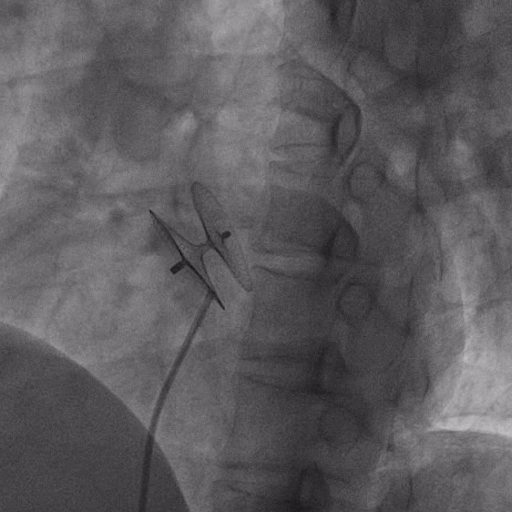

在獲得患者同意后,1月12日,尚福軍主任為患者進行了PFO封堵術。術中造影可見封堵器殘余漏,尚福軍主任用精湛的技藝,順利通過封堵器殘余漏裂縫,將右心導管從右房送入左房,且順利到達肺靜脈;遂行卵圓孔未閉封堵術后殘余漏再次封堵;且完美釋放PFO封堵器,可見兩封堵器呈“馬蹄蓮”狀,再次術中造影未見殘余漏。

術后,小鞏生命體征平穩(wěn)。相關檢查顯示正常,且術后完善心臟彩超及發(fā)泡試驗,可見封堵器位置良好,未見右向左分流,發(fā)泡試驗陰性。